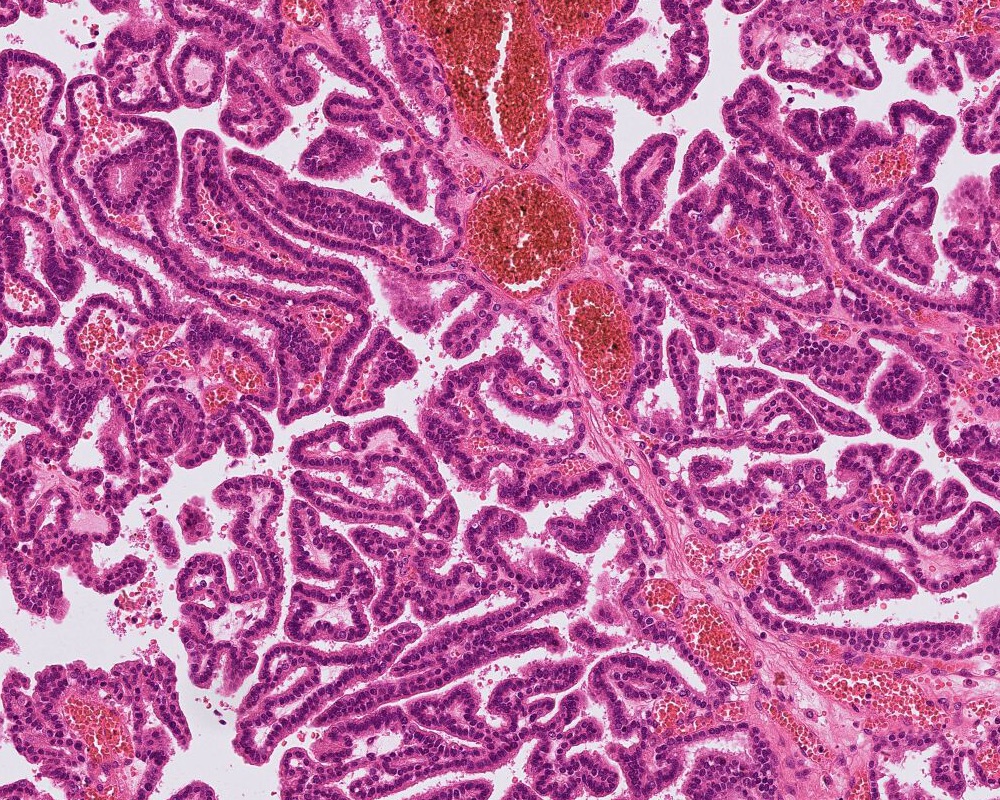

Microscopic (histologic) description

- Choroid plexus papilloma (CPP, WHO grade 1):

- Papillary (finger-like) architecture, resembling normal choroid plexus

- Single layer of cuboidal to columnar monomorphic cells

- Loss of cobblestone surface

- Mild nuclear pleomorphism, mitotic activity rare (< 2/10 high power fields), lacks necrosis

- Atypical choroid plexus papilloma (aCPP, WHO grade 2):

- Higher cellularity relative to CPP

- Moderate nuclear pleomorphism, blurring of papillary pattern

- Occasional mitoses (> 2/10 high power fields), with or without necrosis

Microscopic (histologic) images

Board review style question #1

A 3 month old boy presented with restless crying and vomiting. His head size was larger than expected for his age. Imaging showed an 8 cm, lobulated, enhancing lesion in the right lateral ventricle. Histology is as above. Which of the following is true?

Board review style answer #1

B. Recent studies suggest 3 distinct molecular entities based on methylation profiling, patient age and tumor location. An atypical choroid plexus tumor is shown in the image.